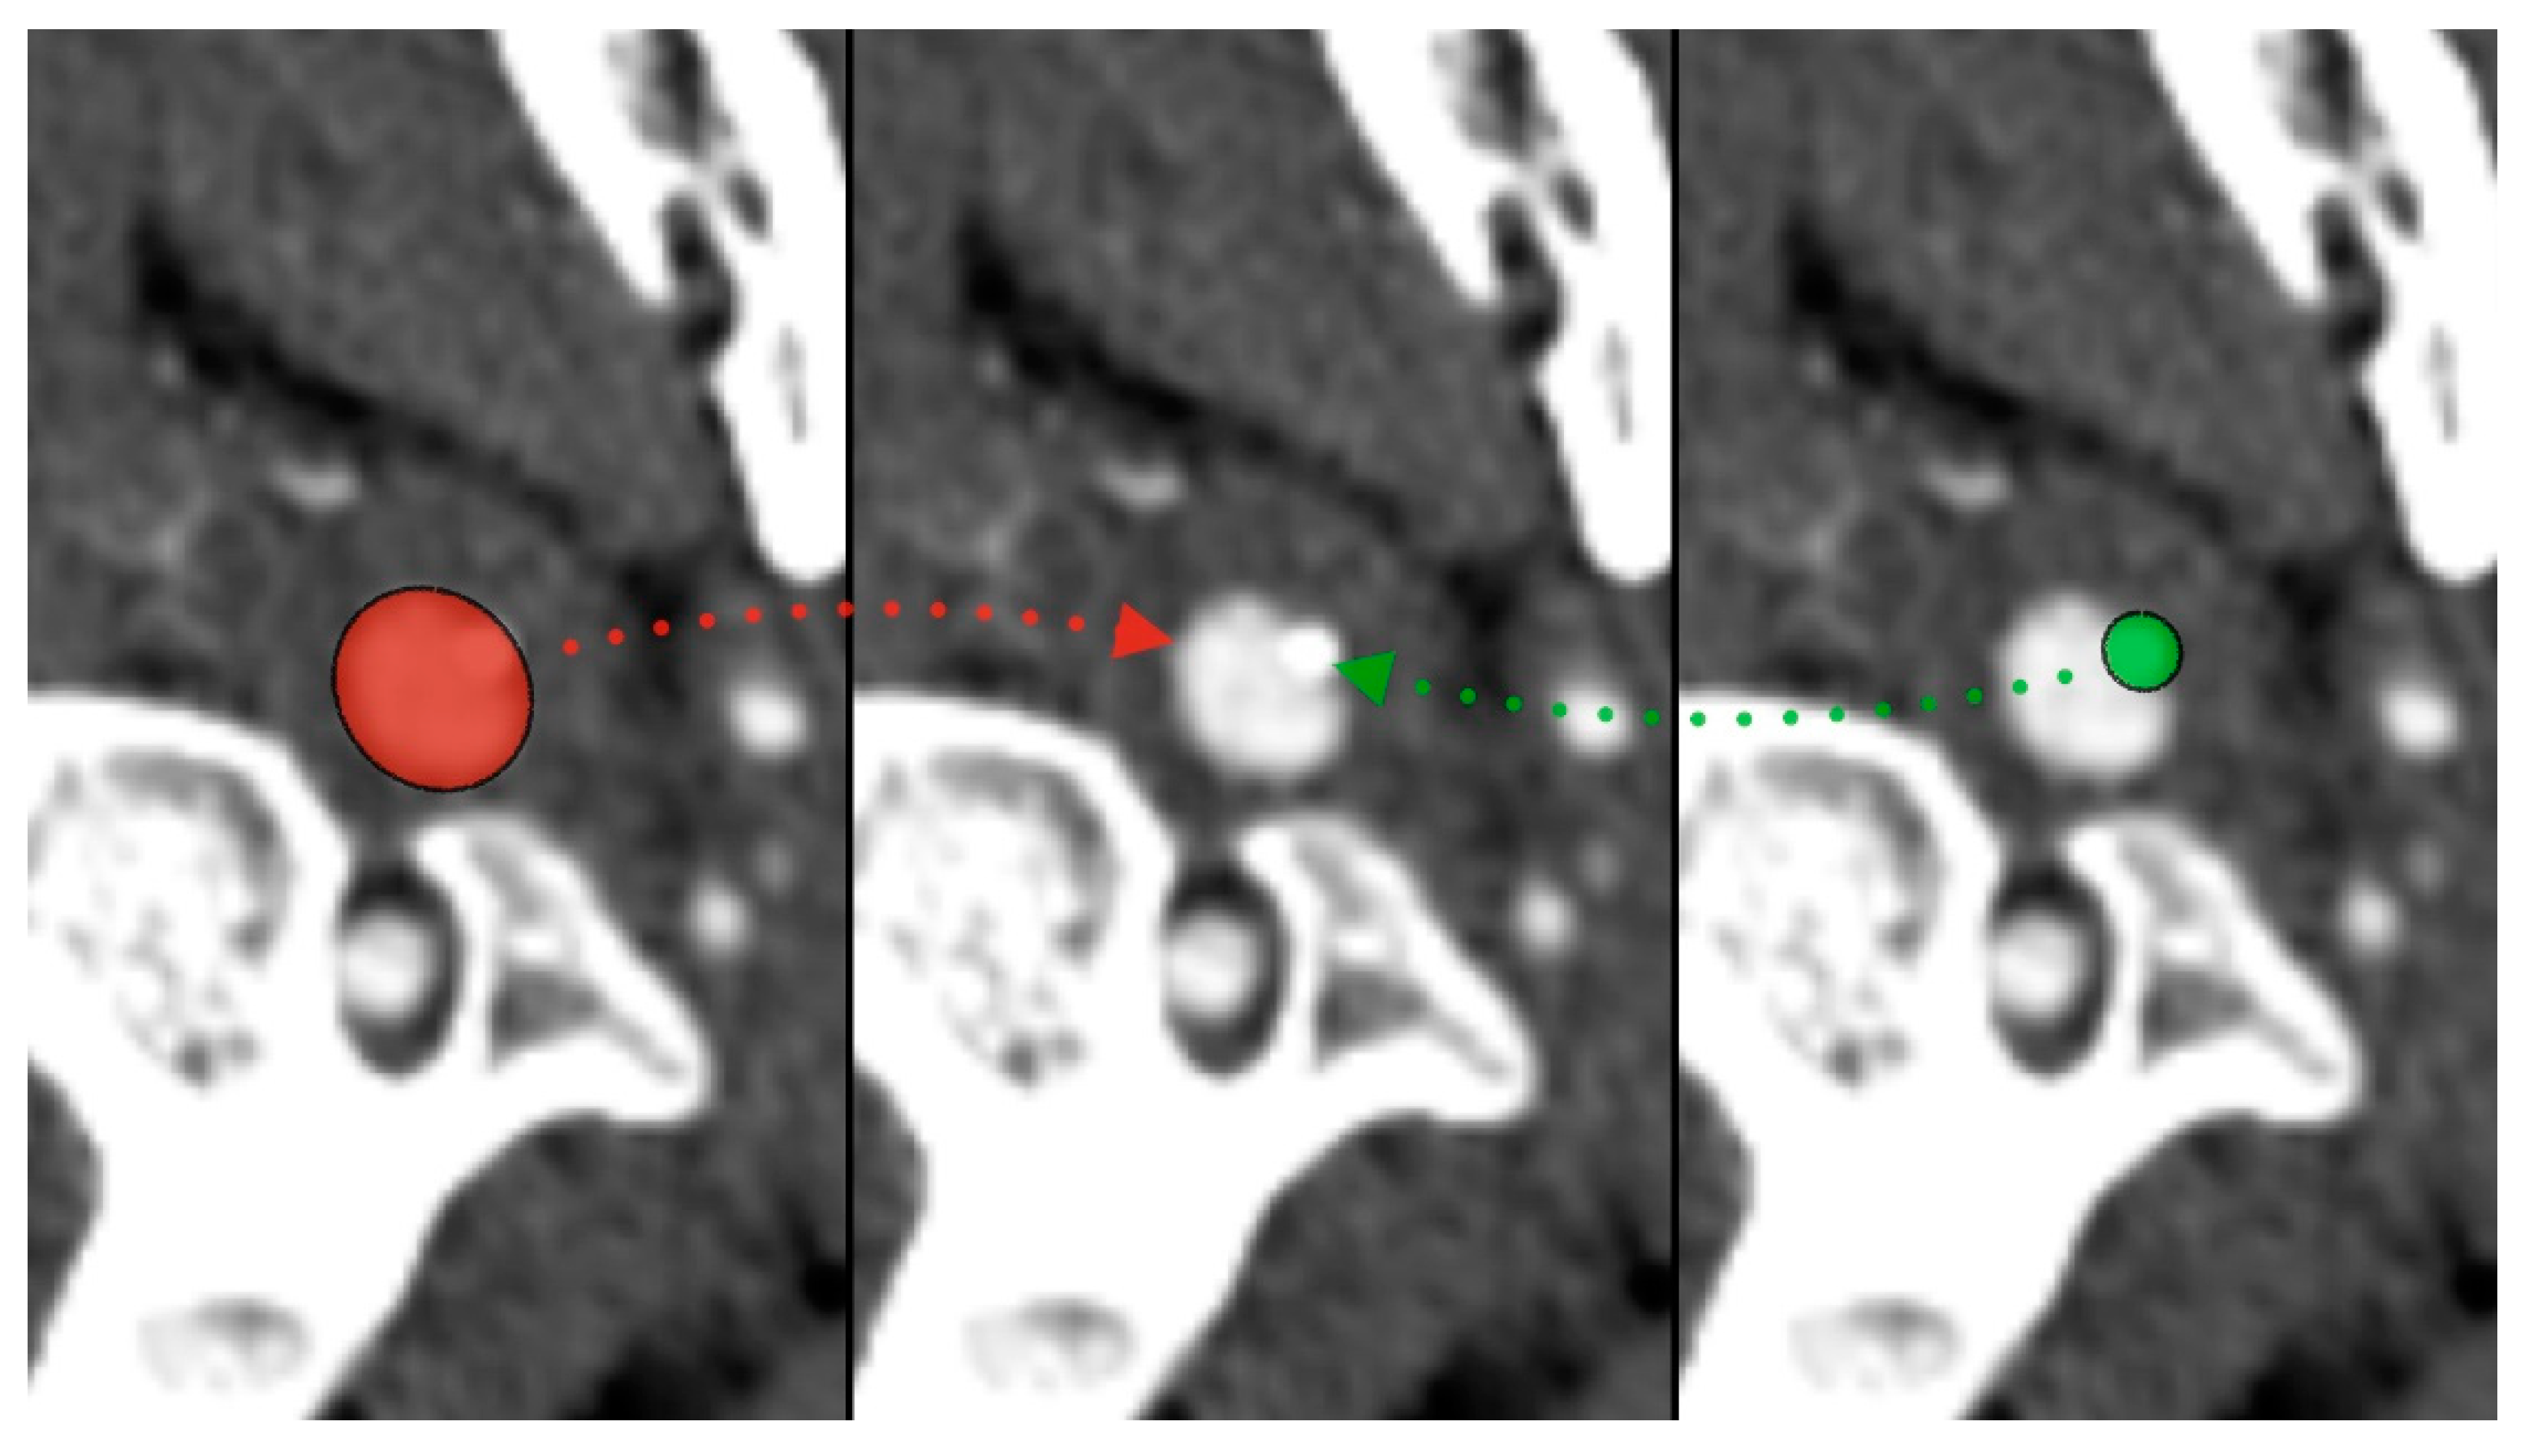

During the CT angiography (CTA) evaluation of thrombolytic treatment, the radiologist identified a bony structure that reduced the diameter of the left internal carotid artery (LICA) from 14 to 7 mm. Three-dimensional reconstruction identified the styloid process, measuring 29 mm, compressing the vessel (Figure 1 and Figure 2). Vascular surgeons suggested LICA decompression without stenting. Consequently, the patient was qualified for styloidectomy and was transferred to the Cranio-Maxillo-Facial Department.

Figure 1.

Styloid process compressing left internal carotid artery—red (ICA), green (styloid).